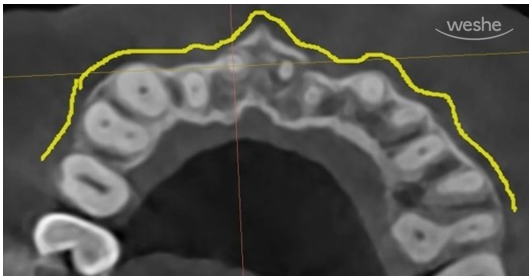

CT 사진입니다.

환자의 머리 위에서 바라보고 있는 방향입니다.

무엇이 보이나요?

노란선은 우리의 잇몸뼈 바깥경계선을 따라 그린 것입니다.

X-ray상에서 진한 흰색선으로 보이지요.

다른 부위에서는 잇몸뼈(치조골)가 연속적으로 잘 이어져 있는 반면,

빨간색으로 표시된 부위에서는 뼈의 윤곽선이 뚜렷하게 끊겨 있는 모습을 볼 수 있습니다.